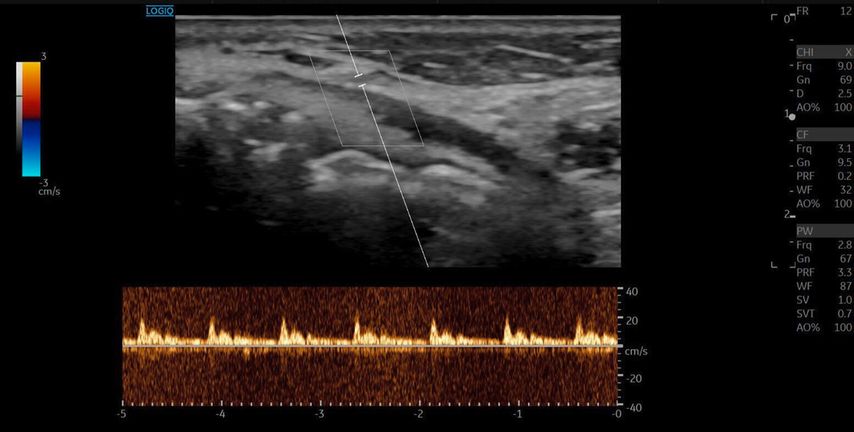

Die A. facialis imponierte beim Austritt im Bereich des Musculus masseter (oberhalb der Kieferlinie) vasospastisch mit einem maximalen Durchmesser von 1mm. Die abgeleitete systolische Spitzengeschwindigkeit betrug trotz der bestehenden Ischämie 20cm/s, ohne enddiastolische Komponente, was auf eine weitere periphere Vasokonstriktion hindeutete (Abb. 2 und 3).